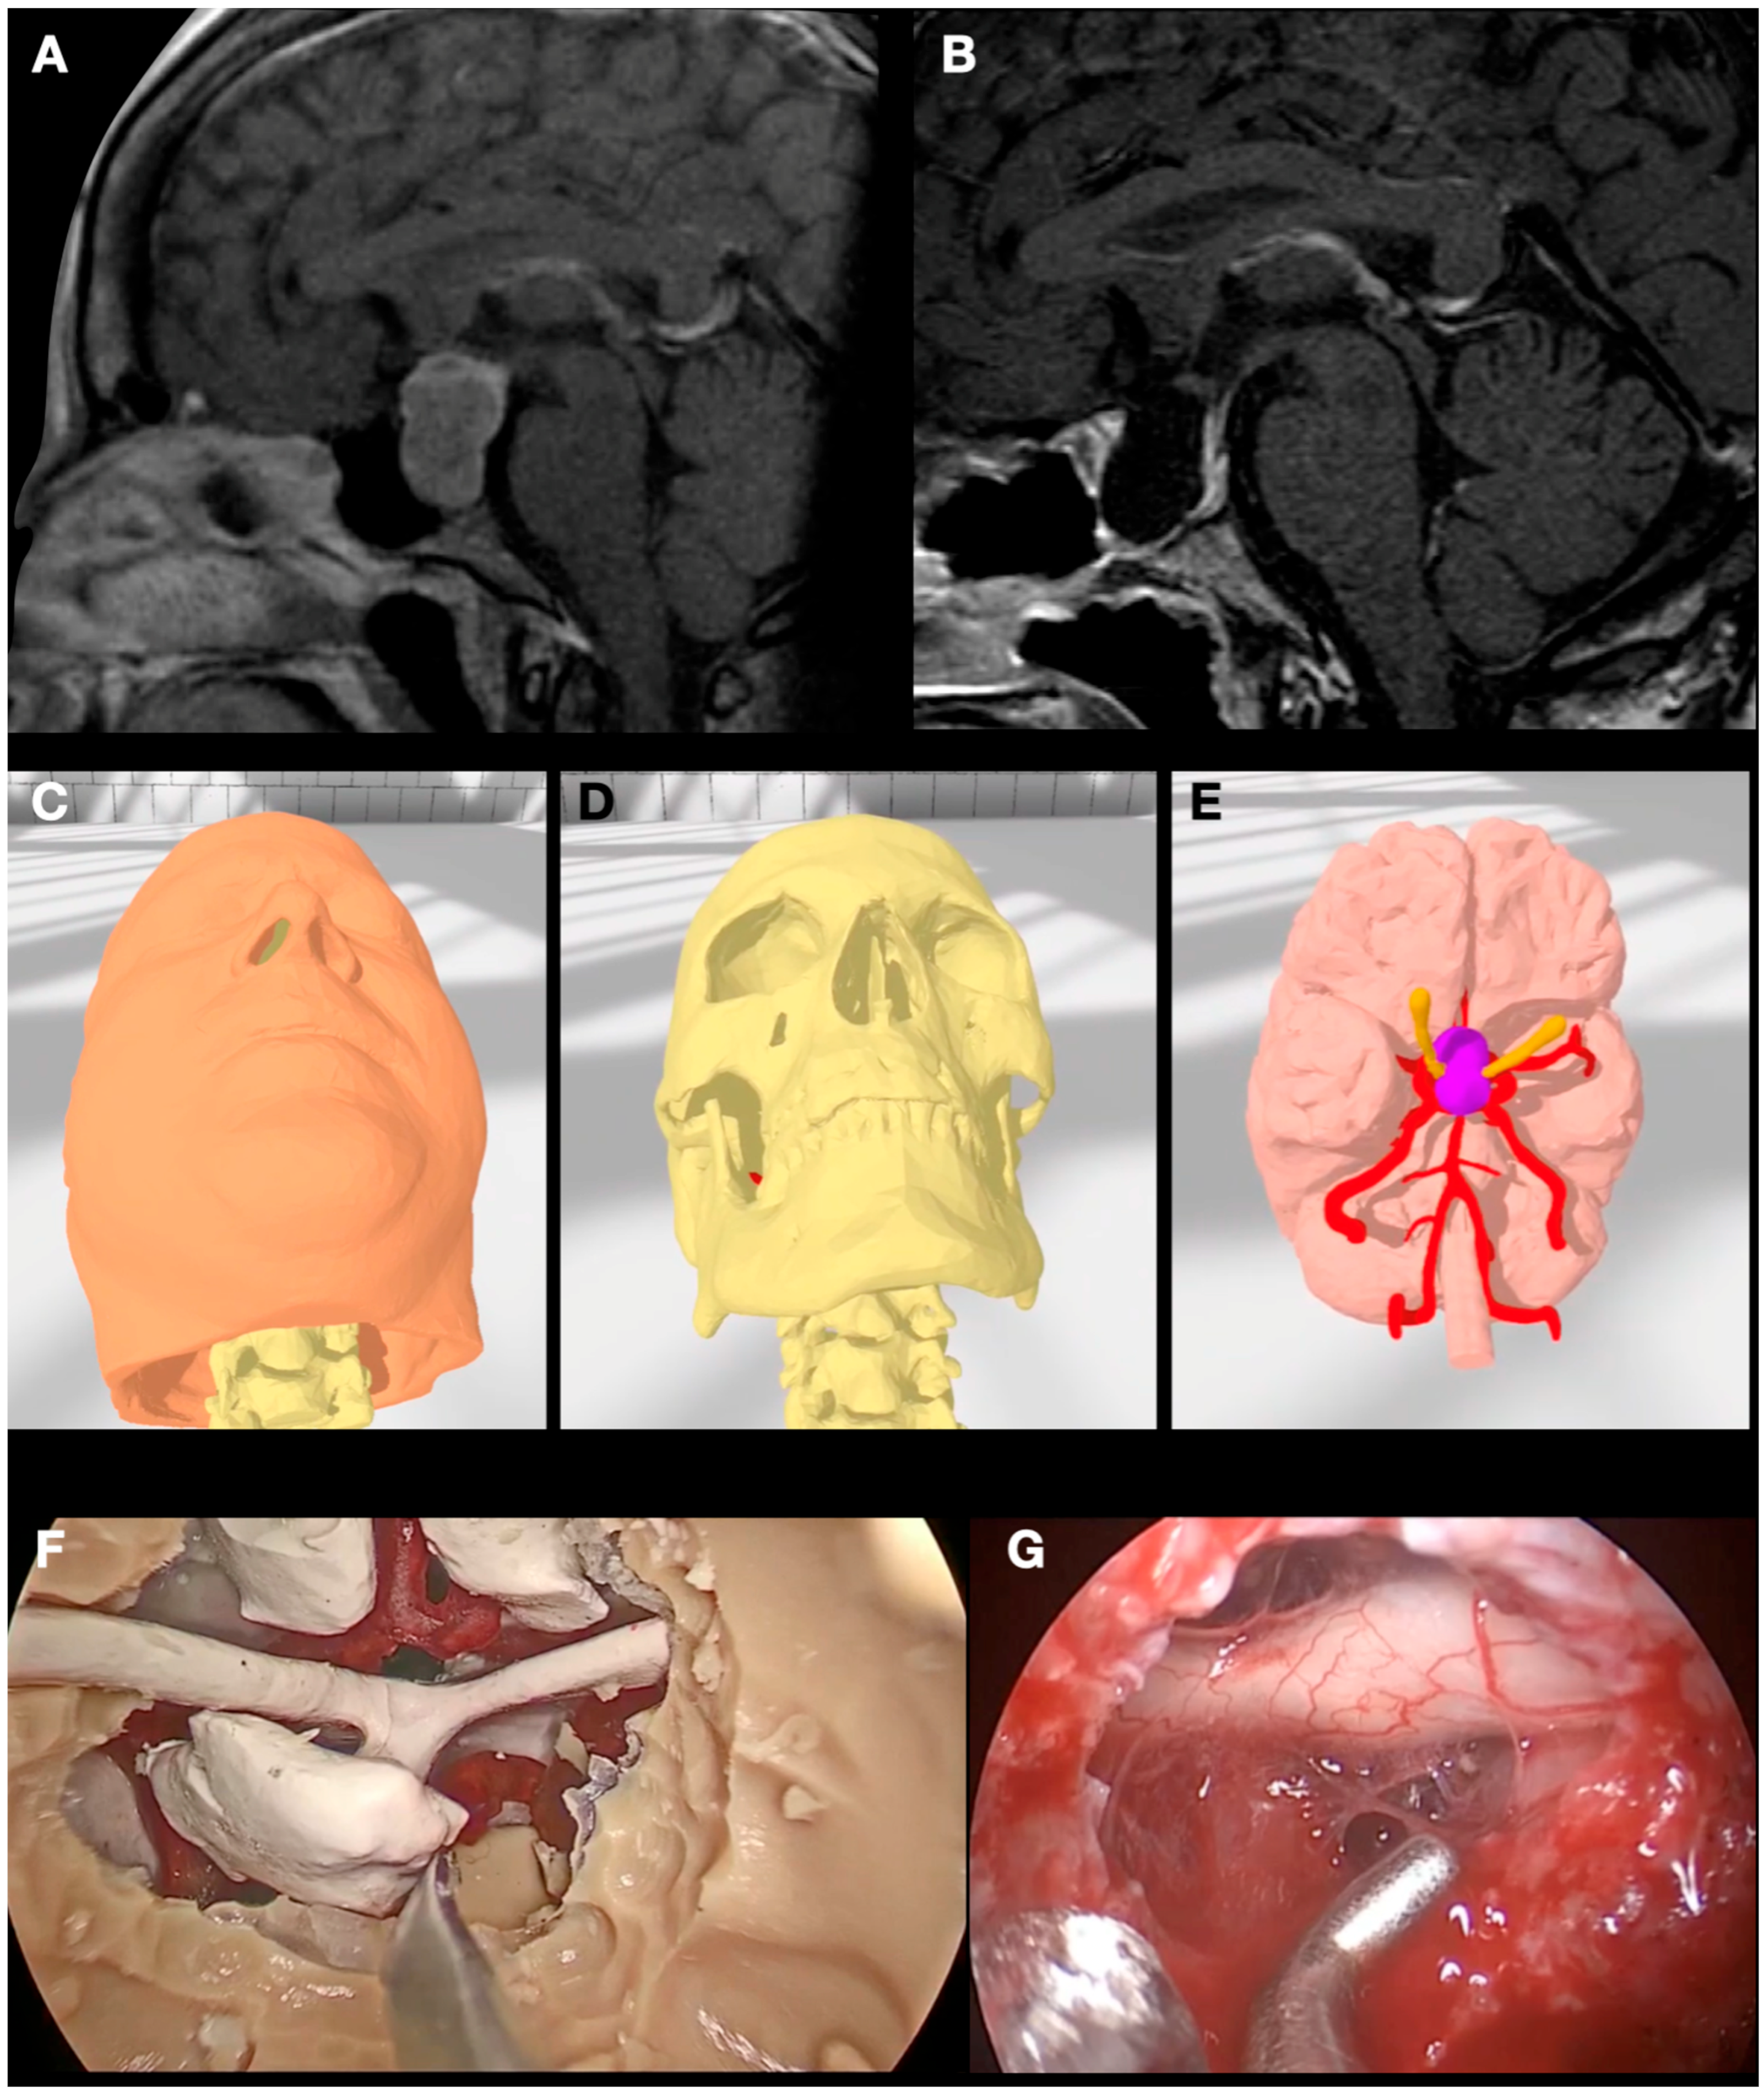

3.2. Case 2: Pituitary Adenoma